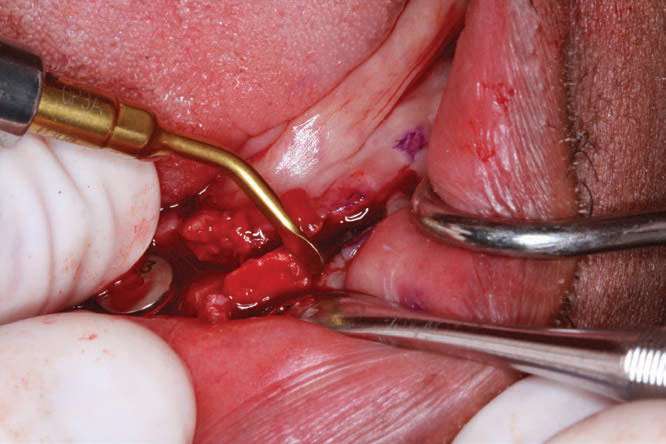

BioHorizons implants were selected in order to increase bone-implant contact, as the threads are designed to optimize bone contact as well as utilize Laser-Lok technology (BioHorizons) to hold the hemidesmosomes of the tissue so that the tissues would be less friable and provide for better tissue dynamics. Upon implant placement, a Piezo surgical device (PIEZOSURGERY by Mectron) was used to remove sharp lips of bone as the implants were countersunk by design. The PIEZOSURGERY by Mectron works by using micro-vibrations to cut bone while minimizing soft-tissue trauma. The device and its internal irrigation provides an almost blood-free foundation while cleaning around the implants and removing unwanted tissues. The cutting is micrometric, and the micro-vibrations not only cut bone but help collect bone particles to be used in the defects around the implants so the autogenous shavings can be placed adjacent to the exposed threads or fenestrations[14] (Figure 7).

The BioHorizons implants were placed with a good A-P spread, and the bone in the anterior mandible was left in case it was needed at the uncovery appointment (Figure 8). At the uncovery visit, the LightScalpel laser was used to perform a trephine of the posterior implants by placing the surgical guide, marking the osteotomy sites with a Dr. Thompson’s marking stick, and (using a super-pulsed 2W setting) to gently remove the cuff of tissue over the implants (Figure 9). In the anterior mandible, a full-thickness flap was done, and the remaining bone was removed with the PIEZOSURGERY device (Figure 10). The peri-mucosal healing abutments were placed, and a soft-tissue conditioner was placed in the lower denture (Figure 11). After one month of healing, the patient was ready for impressions (Figure 12).